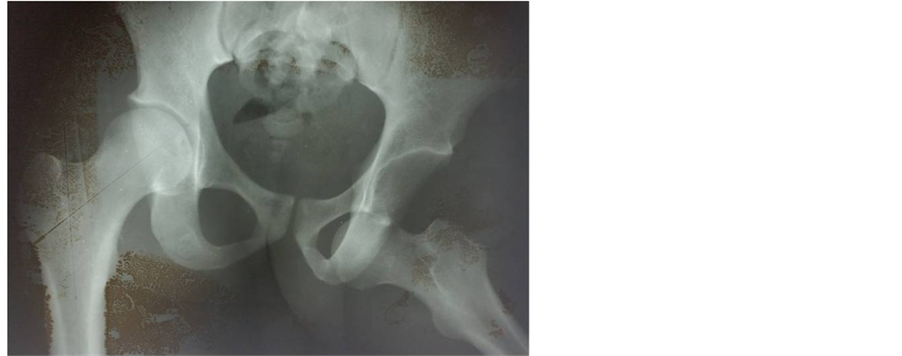

Mr. CA was a 26-year-old patient who was hospitalized on February 7th 2004 for a right hip injury following a road traffic accident. He had no medical history and in the circumstances of the accident, he was carrying his cart from the front when a car hit the back of his cart. Immediately, he felt a sharp pain and an absolute functional impotence of the limb. Clinical examination of the same limb revealed abduction, an external rotation and flexion at the hip. Standard radiographs confirmed obturator dislocation (Figure 2). Closed reduction under general

Figure 2. Anteroposterior X-ray of the pelvis showing a left obturator dislocation (patient 2).

anaesthesia was achieved 24 hours after the injury, followed by 10 days of bed traction. Control plain X-rays obtained 24 months later showed no signs of avascular necrosis.